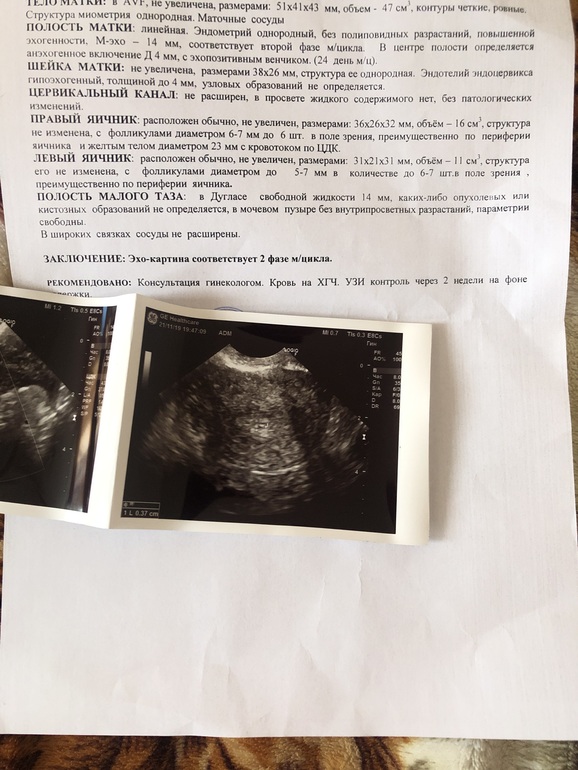

У вас есть задержка?по УЗИ есть шансы на беременность,жёлтое тело хорошее,кист нет у вас,единственное,много жидкости в позадиматочн.пространстве.Хгч только при беремен.вырабатывается.

Норма до 8 (у вас 14) чаще всего в норме появляется после овуляции,и то,быстро потом в течение суток рассасывается. А так при воспалении бывает.Может узист ошиблась...

Яичники по УЗИ спокойны,не увеличены у автора. Да причин очень много,про воспаление и не утверждала,это как пример.

А сколько у Вас акушерских недель? И сколько хгч показывает? 10.12 - это хгч? Если да, то вряд ли при таком хгч будет ПЯ вообще видно. А так, если у вас маленький срок Б (до 5 недель например), то конечно узист так скажет и напишет.

Я ещё не знаю сколько , узостей точно не сказала ничего , хгч 10.12 да , сначала сделала узи , потом сдала хгч на следующий день

Тут 2 варианта, либо Вы с цифрой хгч напутали и у Вас хгч 1012 (а не 10.12) и тогда это Плодное яйцо в 4 мм, либо на узи это ещё не ПЯ.

Я когда пошла первый раз на узи, у меня нашли ПЯ 2 мм, при хгч 509, а у вас уже 4 мм и они не знают что это... Но при хгч 10,12 ПЯ 4 мм не может быть, такой размер ПЯ когда хгч уже за 1000.

Хгч 10 это примерно 8-10 дней от овуляции и срок совсем маленький 3 недели,на УЗИ надо идти,когда хгч будет больше 1 тыс,а пока сдавайте хгч в динамике

При таком хгч УЗИ не может показать беременность,это невозможно,да это беременность,но очень-очень маленький срок

Анэхогенное включение что-то великовато для хгч 10, но это еще не значит, что Б нет, мне кажется. Все правильно написали в заключении. По поводу этого включения, надо переделать узи еще раз, по поводу развития Б еще раз сдать хгч.

Во время беременности матка должна быть увеличена и полость матки при беременности рыхлая, а у вас ни того ни другого нет. У меня уже трое детей и у двух сестёр тоже по трое деток, так что судя по УЗИ у вас беременности нет, и это точно